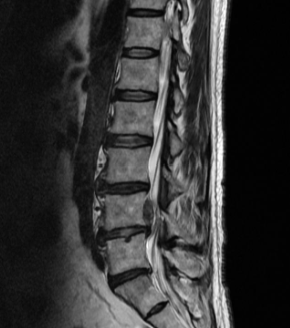

허리디스크를 올바르게 진단할려면 엑스레이로는 힘들며, MRI를 통해 검사해야 올바르게 볼 수 있습니다.

MRI가 몸에 좋지 않지만 허리 통증으로 엑스레이만 진행 할 경우 오진이 많아 계속적인 고통이 계속 된다면 허리디스크를 의심하고 MRI 검사를 한번 받아보시길 권유드립니다.